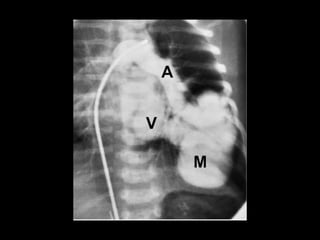

Sequestro intralobar com infecções recorrentes

Sequestro pulmonar Definição:segmento de tecido pulmonar que é separado da árvore brônquica e recebe seu suprimento sanguíneo de uma artéria sistêmica; Dois tipos: intralobar e extralobar; A maioria dos sequestros são tipo intralobar; O suprimento vascular em 80-90% dos casos provêm da artéria aorta descendente; Complicações: hemoptise e BCP repetição; Diagnóstico: identificação do vaso anômalo.

Sequestro intralobar cominfecções recorrentes